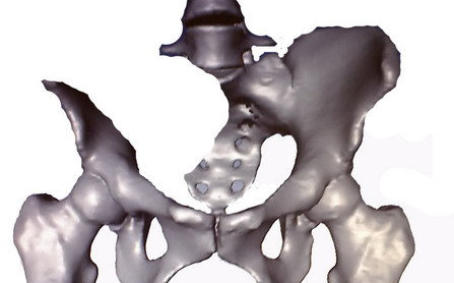

vermelden. Ich erinnert euch alle an die Bilder, die wir euch nach der Operation gezeigt haben. Hier ist es auf dem Foto noch einmal zu

sehen. Es ist ihr operativ das rechte Wadenbein aus dem Bein entfernt und als Stütze in das Becken eingesetzt worden, dort, wo vorher

die Beckenschaufel war. Das ist schon ein Meisterwerk ärztlicher Kunst gewesen. Und Gott hat Gelingen und Segen dazu gegeben. Die

Schmerzen, die Puschel in den letzten Tagen mehr hatte als sonst, rühren jetzt daher, dass der Knochen etwa an der Stelle, auf die der

Pfeil zeigt, richtiggehend durchgebrochen ist. Die Ärzte sprechen von einem Ermüdungsbruch. Der Knochen ist in der Substanz während

der Zeit der Chemo und der dadurch beabsichtigten Verhinderung der Neubildung von Zellen (Zielpunkt waren natürlich die

Krebszellen) zurückgegangen und ermüdet. Das große Problem ist, dass nun noch weniger Stabilität da ist und der Knochen erst wieder

zusammenwachsen muss. Darum werdet ihr, wenn ihr hier reinschaut, nun wieder mehr Bilder von “Puschel im Liegen” sehen. Das ist